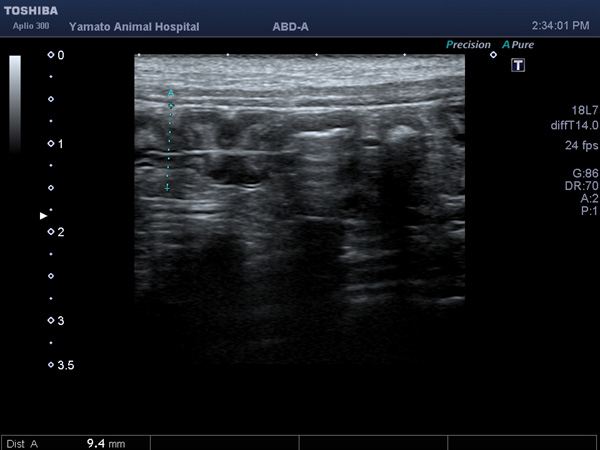

吐き気が続いて、元気・食欲がないワンちゃんが来院されました。超音波検査で異物による小腸閉塞、特にひも状異物が画像から疑われましたので緊急手術となりました。腸を切開し異物を摘出し、無事手術は終了、元気に退院していきました。よかったね。